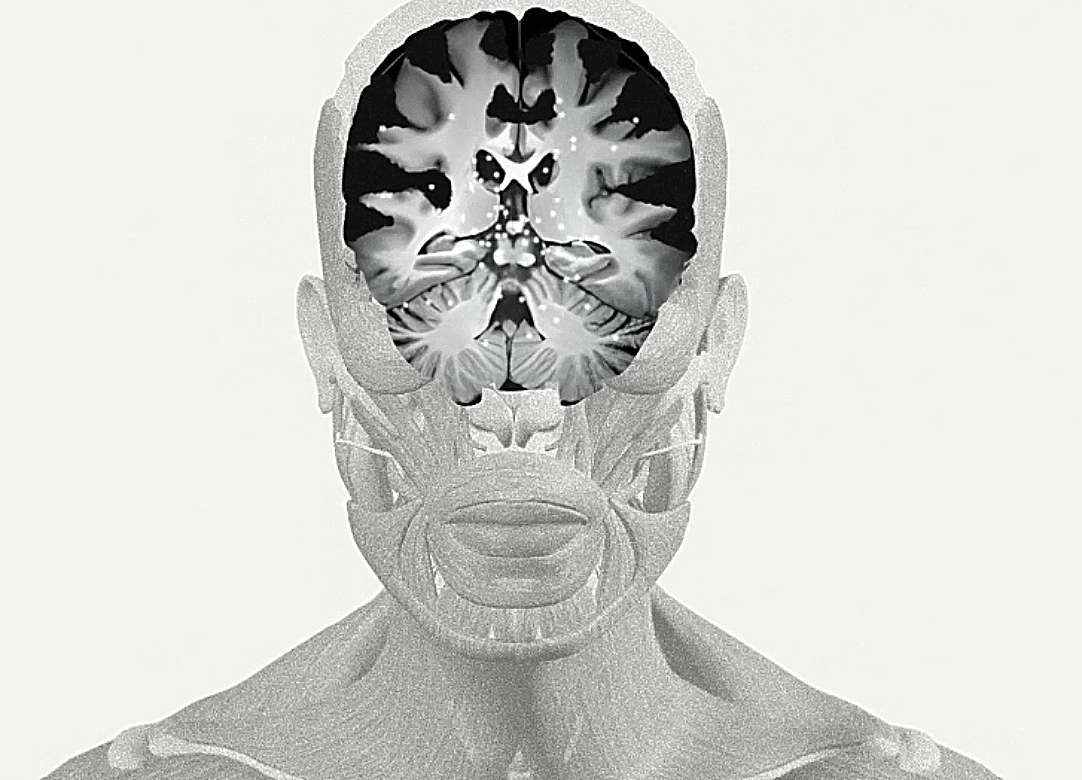

Η πολυπλοκότητα του εγκεφάλου

Ο εγκέφαλος θεωρείται το πιο πολύπλοκο όργανο του σώματος, καθώς λειτουργεί σαν το κέντρο δεδομένων για κάθε λειτουργία του οργανισμού. Ενώ είναι αναμενόμενο να εξελίσσεται με την ηλικία, είναι πραγματικά συναρπαστικό να βλέπει κανείς την επιστημονική εξήγηση πίσω από αυτές τις αλλαγές.

Ο εγκέφαλός αρχίζει να σχηματίζεται μόλις δύο εβδομάδες μετά τη σύλληψη. Μέχρι την τέταρτη εβδομάδα σχηματίζεται ο νευρικός σωλήνας, ο οποίος εξελίσσεται στο νευρικό σύστημα.

Από εκεί και πέρα, ο εγκέφαλος αναπτύσσει συνεχώς νευρικά κύτταρα που ονομάζονται νευρώνες. Κατά τη γέννηση, έχουμε περίπου 100 δισεκατομμύρια νευρώνες, περισσότερους από οποιαδήποτε άλλη στιγμή στη ζωή σου.

Ωστόσο, καθώς μεγαλώνουμε, ο αριθμός των νευρώνων μειώνεται. Αντί αυτών, ο εγκέφαλός αναπτύσσει συνάψεις, που επιτρέπουν την επικοινωνία μεταξύ των νευρώνων, ενώ η μυελίνη, ένα λιπαρό μονωτικό υλικό, βελτιώνει τη μετάδοση των πληροφοριών και επιταχύνει την επεξεργασία δεδομένων.